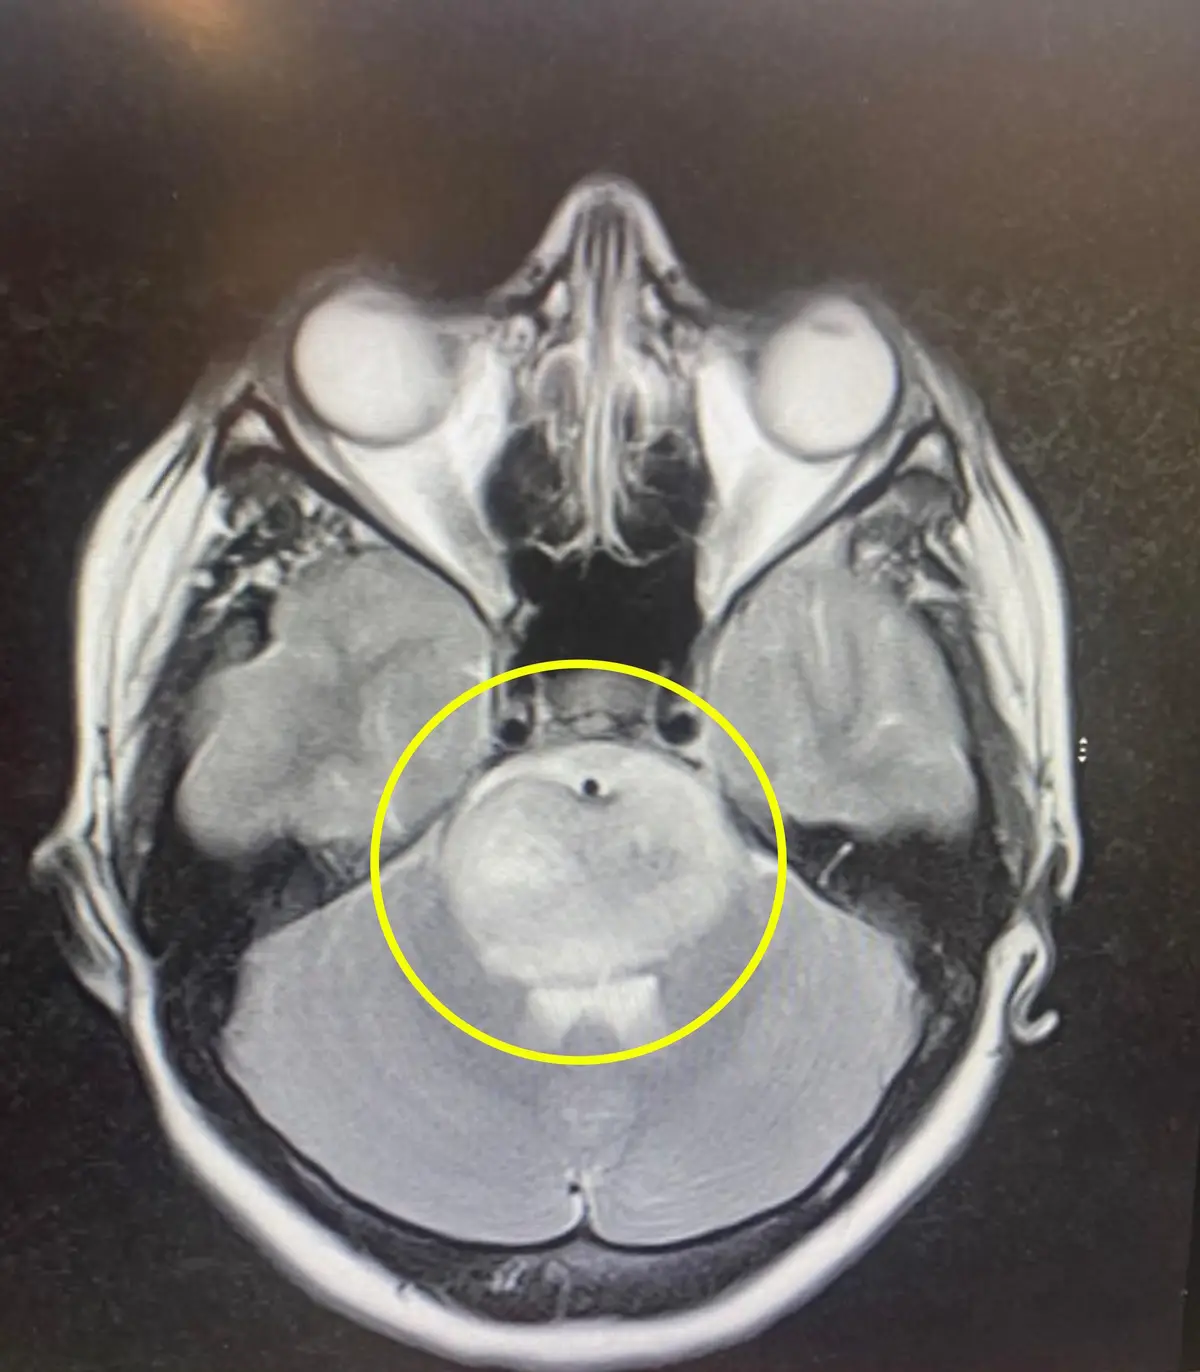

Doctors at Pilgrim Hospital in Boston, Lincolnshire, found a lump on Ella's brain after CT and MRI scans - 'a diffuse midline glioma' on her brain stem.

"They can't exactly say how long I have because I can't have a biopsy because of where the tumour is. If I were to have a biopsy, they would more than likely paralyse me so they can't exactly say how many months I have."